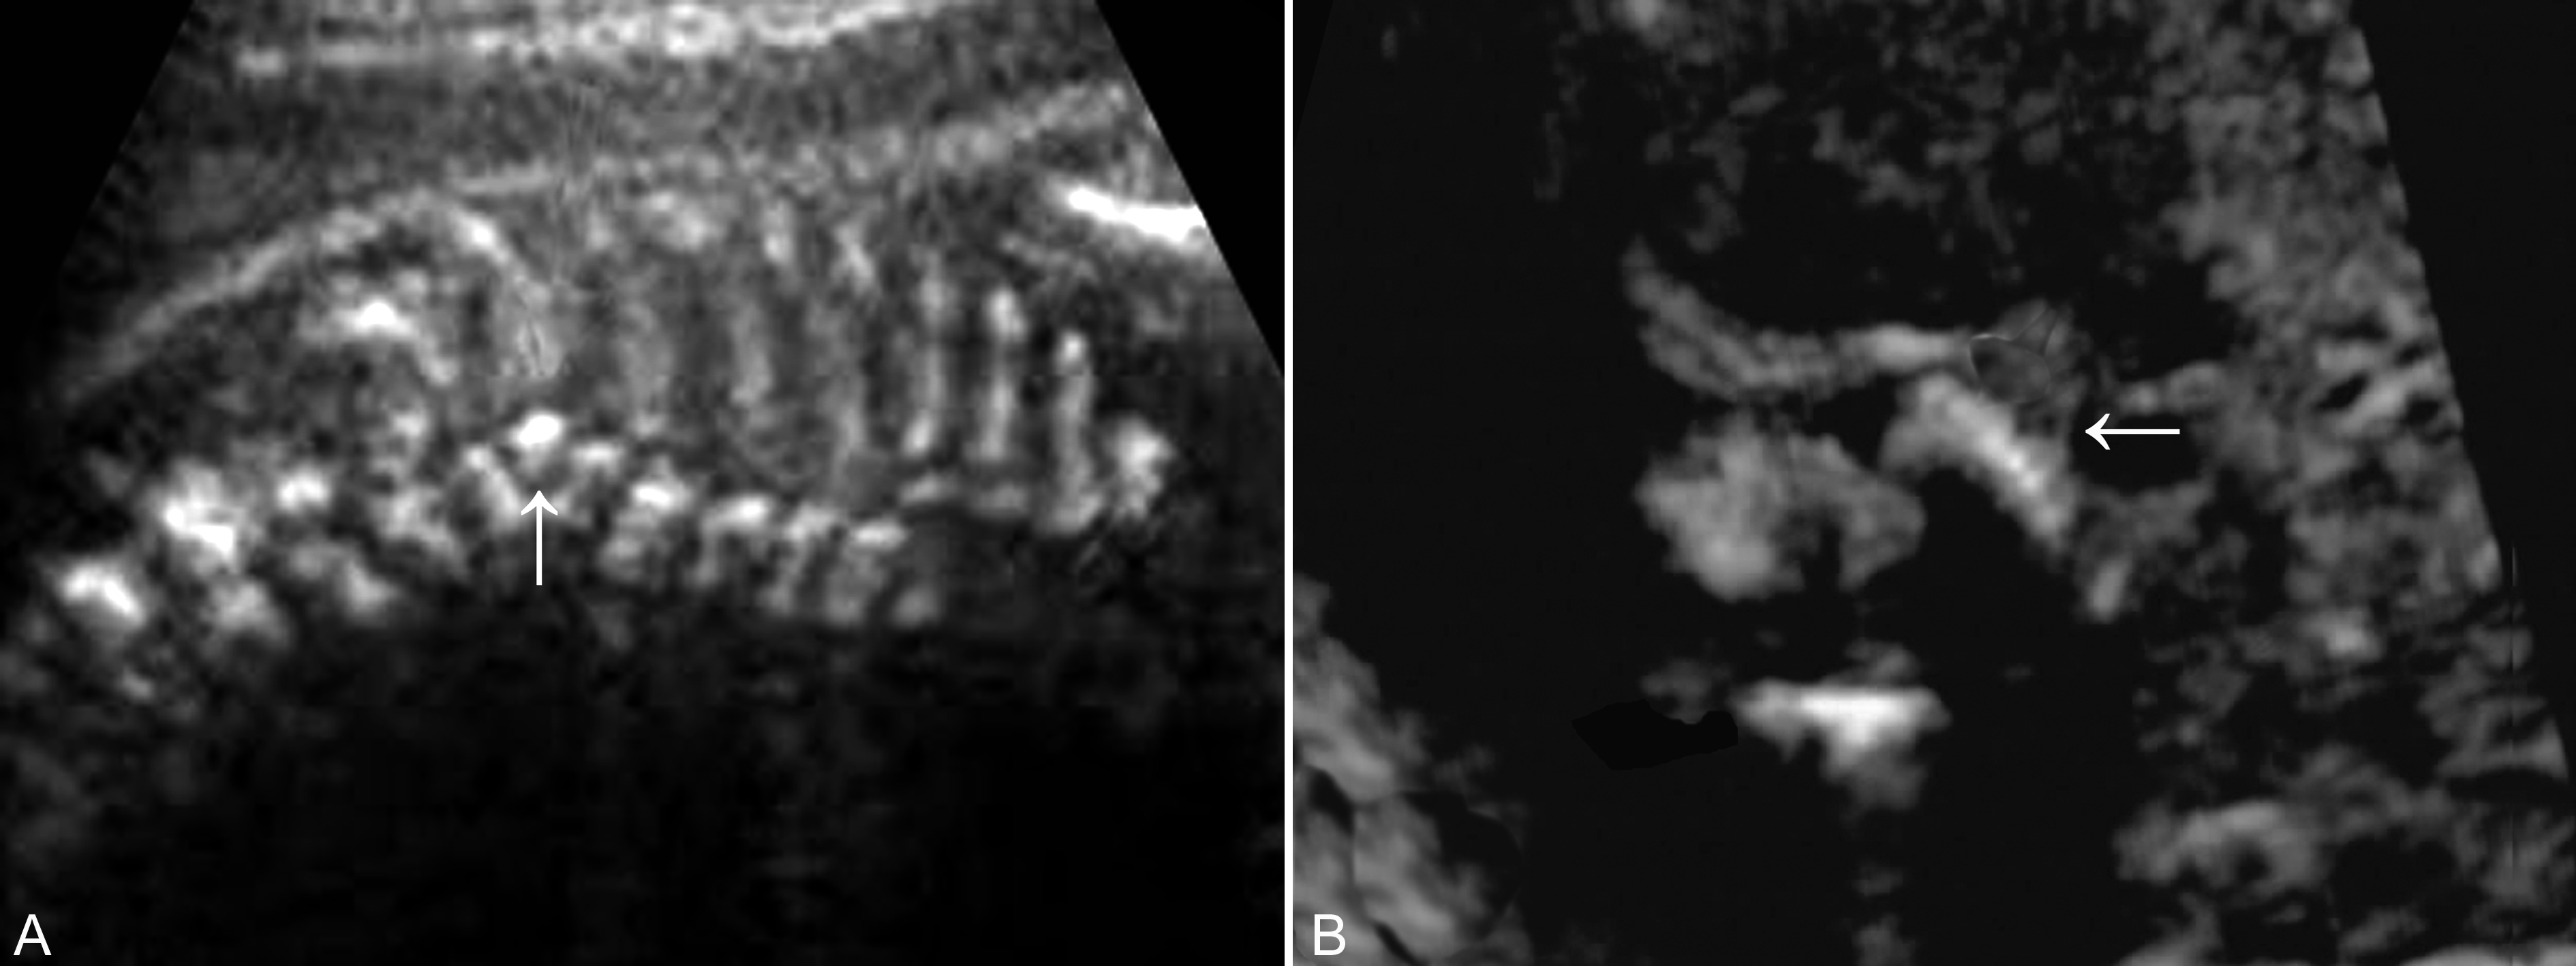

超声显像检查常常在发现脊柱异常弯曲及回声异常为线索显示半椎体畸形。脊柱矢状面扫查显示脊柱表面皮肤完整,脊柱两条带状强回声失去正常的串珠状平行状态,排列不整齐,局部强回声明显缩小呈三角形或楔状嵌入在椎体强回声带中,局部脊柱弯曲或成角畸形(图2A、B);病变可以累及一个或多个椎体。冠状切面显示局部椎体骨化中心较小、移位,与其他椎体失去正常的排列关系,局部形成脊柱成角的顶点;脊柱横切面显示脊柱的骨化中心的三角形的排列关系,其中一个骨化中心不能显示。

图23-18胎儿半椎体畸形:A:冠状面显示半椎体(箭头);B:横断面可见部分椎体(箭头)